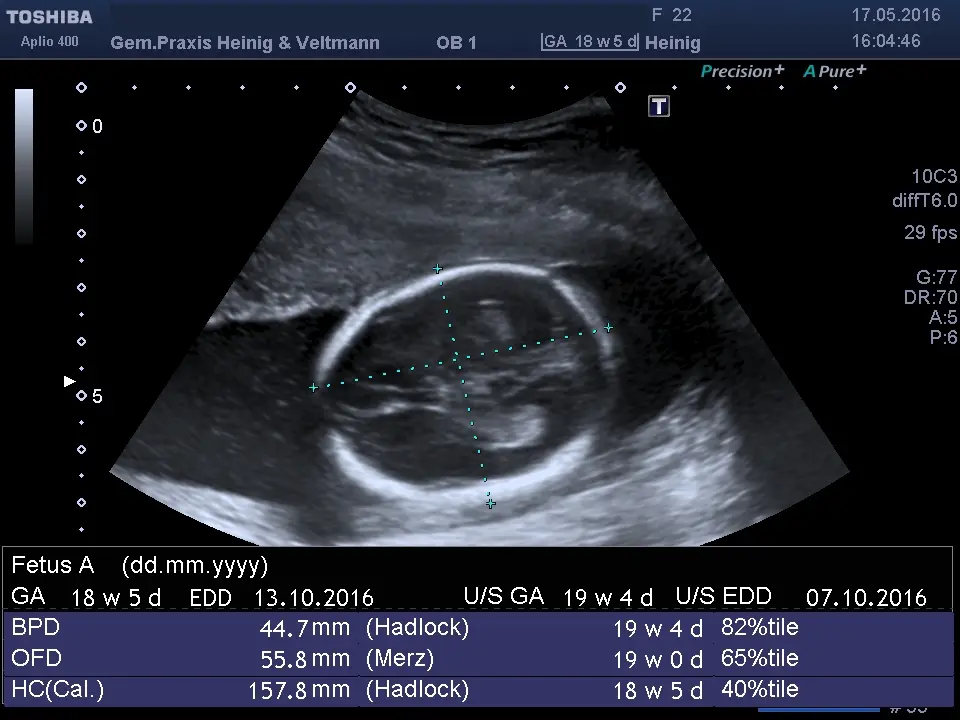

Gibt es eine Möglichkeit, das GA meines Kindes zu überprüfen?

Es gibt verschiedene Methoden, um das GA Ihres Kindes zu überprüfen. Ihr Arzt kann eine Ultraschalluntersuchung durchführen, um das GA Ihres Kindes zu bestimmen.